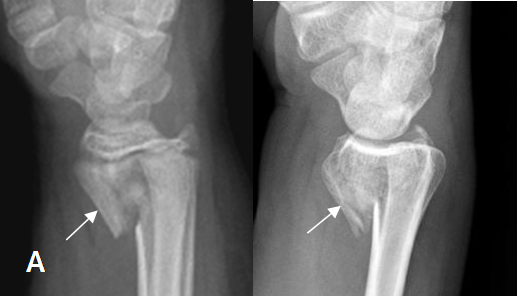

Q

Que es?

A

BARTON